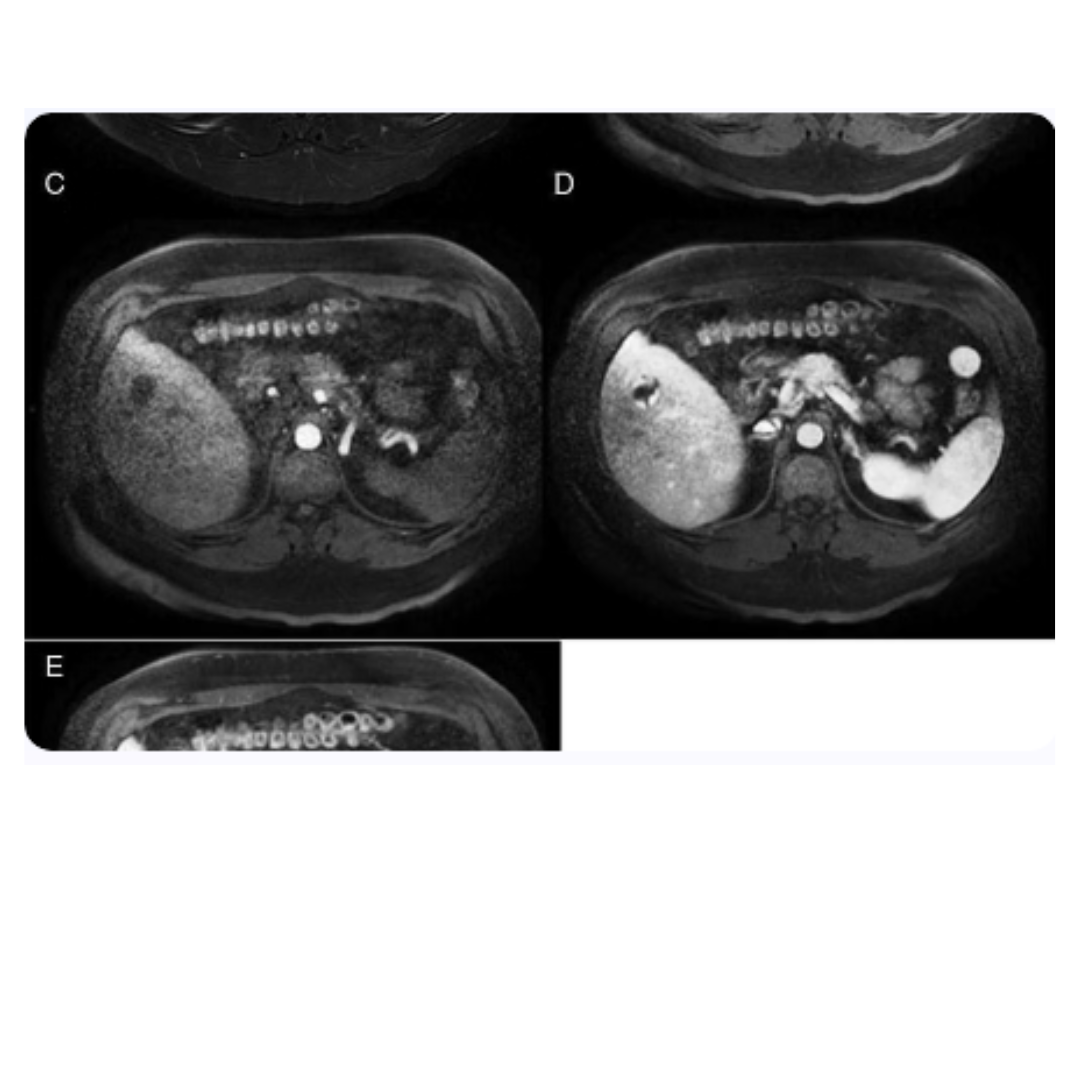

9. Estudios de imagen en el diagnóstico de la leucemia linfocítica aguda

Resonancia magnética cerebral

Ecografía doppler de órganos abdominales

La ecografía Doppler es otro método de imagen no invasivo, esencial para la evaluación de la arquitectura y la vascularización de los órganos abdominales en pacientes con LLA. Este procedimiento es significativamente útil para detectar esplenomegalia, hepatomegalia y alteraciones en los órganos que podrían sugerir infiltración leucémica o complicaciones secundarias a la enfermedad o su tratamiento.